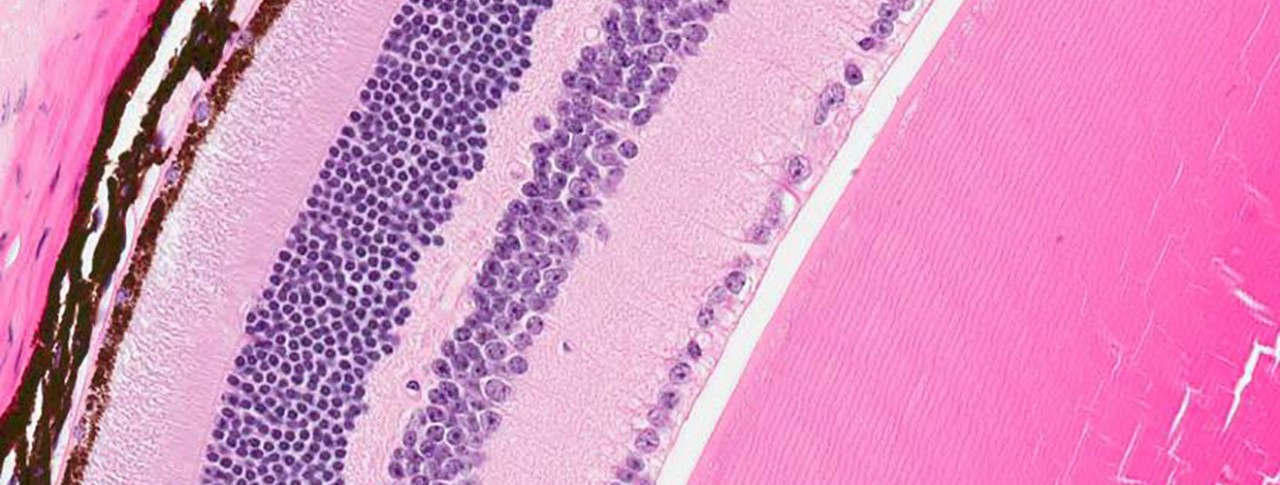

Morgan has retinitis pigmentosa (RP), which is a rare inherited disorder that cripples light-sensing cells in the retina (a layer of tissue in the back of the eye). Though it leads to visual problems in all patients, RP has varied genetic causes. In Morgan’s case, the culprit is a defective RLBP1 gene, which can’t make a crucial protein that light-sensing photoreceptor cells in the retina need to function properly. When deprived of that protein, the cells falter and eventually die, resulting in total blindness.

Main image: Novartis researchers designed a gene therapy aimed at repairing the protein-making machinery of diseased retina cells (some shown in brown) to potentially preserve visual function in patients with a rare disease. Image by Oliver Turner/Novartis